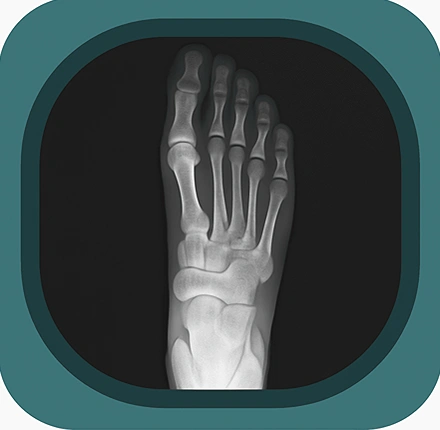

Explore high-quality X-ray anatomy from head to toe. Our database features carefully labelled images to visualize fine structures—perfect for radiologists, students, and surgeons.